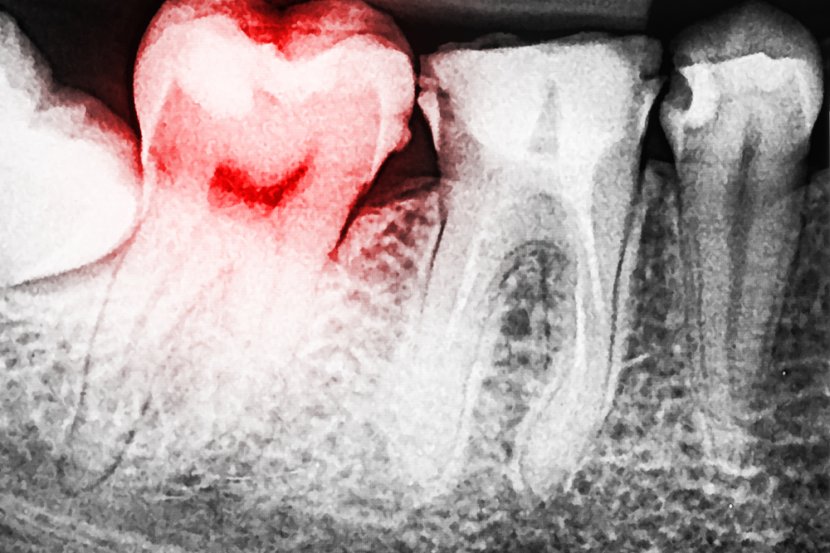

− Pored ovih problema, ozbiljniji problem, koji može biti izazvan zapuštenim ustima, jeste negativan uticaj na zdravlje celog organizma. Ono što se nekom čini kao banalna stvar, kao npr. zubni kamenac, karijesi koji dugo stoje… upravo može biti put ka mnogim sistemskim bolestima ili problemima koji se javljaju u nekim udaljenim organima. Evo zašto je to tako: zapušteni karijesi, koji vremenom zahvataju tkivo pulpe (u narodu poznat kao zubni živac), a odatle, ukoliko se ne leče, mogu prelaziti dalje kroz koren u koštano tkivo i putem krvi i limfe  u bilo koji udaljeni organ. Kod loše higijene gde su konstantno prisutne upale desni, prisustvo zubnog plaka, kamenca i parodontalnih džepova, postoji veliki broj bakterija, koje se umnožvaju i u tako velikoj koncentraciji dospevaju u krvotok, odakle mogu da stignu u bilo koji deo organizma.

− Suštinski fokalne infekcije su infekcije koje se mogu javiti u bilo kom delu organizma, a izazvane su bakterijama usne duplje ili njihovim produktima. Kod dugotrajnog delovanja bakterija na tkiva i organe, posle izvesnog vremena, dolazi do velikog povećanja broja bakterija usled njihovog razmnožavanja i nastanka dentalnih fokalnih infekcija. Zbog prodora bakterija iz dentalnih žarišta mogu se javiti: bakterijiski endokardit, razne infekcije glave i vrata, oboljenja digestivnog trakta, respiratorne infekcije, koštana i kožna oboljenja, ali i prevremeni porođaji itd.Bitno je naglasiti da saniranjem infekcije u ustima, prolaze simptomi na udaljenim organima. Da bi čitaocima bilo jasnije, evo primera: alopecia areata (lokalizovani gubitak dlake na kosmatom delu glave ili u bradi), koja je nastala kao posledica infekcije u ustima, nakon saniranja zuba potpuno se povlači i popunjava dlakom. Naravno, slično je i sa drugim fokalnim infekcijama, ukoliko svojim dugotrajnim delovanjem nisu dovele do trajnih oštećenja zahvaćenih organa. Koliko su ovo ozbiljne stvari govori činjenica da pre bilo koje intervencije na srcu ili bilo koje vrste transplantacije pacijentima je neophodno sanirati sve infekcije u ustima. − Prodor bakterija u krvotok nije vezan samo za kvarne zube i parodontopatiju, već može biti izazvan i nekim stomatološkim intervencijama. Vađenje zuba, endodontsko lečenje, tretman parodontopatije … takođe mogu prouzrokovati prodor bakterija u krvotok i limfni sistem. S obzirom da su usta jako prokrvljena, a istovremeno i u usnoj duplji ima mnogo bakterija, kod pacijenata koji se mogu nazvati rizičnima (pacijenti sa endokarditom, ugrađenim srčanim valvulama, sveže preležanim infarktom…), neophodna je antibiotska priprema kod svih „krvavih intervencija“, u koje se ubraja i uklanjanje zubnog kamenca.